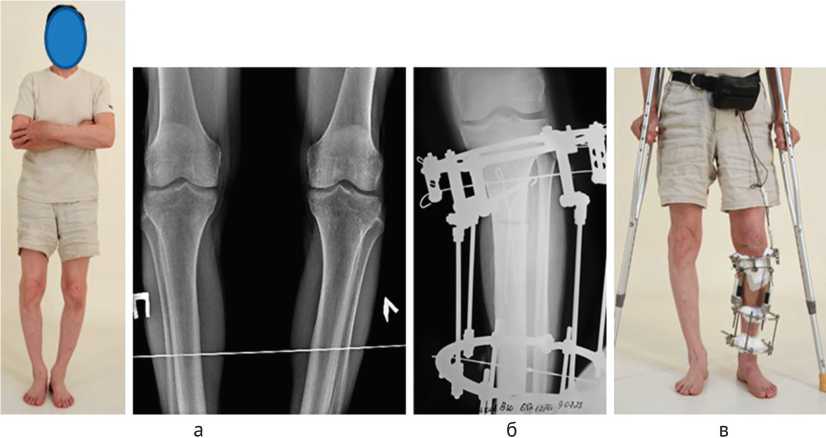

Клиническим примером служит случай исправления варусной деформации большеберцовых костей пациента 65 лет с диагнозом «Врожденная варусная деформация большеберцовых костей 20 ° , гонартроз 2 ст.» методом чрескостного дистракционного остеосинтеза аппаратом Илизарова в автоматическом режиме. Пациент считал, что деформации (рис. 2, а) существуют у него с рождения, и всю сознательную жизнь мечтал их исправить. В последние 2–3 года пациент начал отмечать умеренные боли в коленных суставах. Физически активный образ жизни (военнослужащий) не ограничивал его в регулярных беговых нагрузках, плавании и пешеходном туризме.

Операция (09.07.24) — подмыщелковая частичная кортикотомия левой большеберцовой кости, комбинированный остеосинтез голени аппаратом Илизарова.

Рис. 2. Фотография и рентгенограммы пациента до лечения (а); рентгенограмма костей левой голени после операции (б); фото пациента в процессе автоматического удлинения голени с одновременным исправлением деформации (в)

После операции установили три автоматических дистрактора (ведущий дистрактор — по внутренней поверхности голени, два ведомых дистрактора — по передне-наружной и задне-наружной поверхностям голени) таким образом, чтобы их шарнирные соединения проецировались на уровне продолже- ния биссектрисы угла варусной деформации большеберцовой кости [23]. Дистракцию начали через семь дней после операции темпом 1 мм/сут по ведущему стержню (по 0,025 мм за 40 приемов в сутки). Больной постоянно ходил с костылями, наступая на оперированную ногу (рис. 2, в).

Через две недели аппарат Илизарова был демонтирован после проведения клинической пробы на консолидацию. Общий индекс остеосинтеза (ИО) составил 15 дн/см (рис. 5, в). Функциональная длина левой конечности после исправления деформации превысила правую на 4 см, отеков нет, чувствительность кожных покровов сохранена. Амплитуда движений в голеностопном суставе не ограничена, в коленном суставе — в пределах 120 ° . Клиническая проба на консолидацию не выявила какой-либо подвижности в зоне дистракционного регенерата, что позволило рекомендовать пациенту начинать постепенно возрастающую нагрузку при ходьбе и принять решение об операции по исправлению ва-русной деформации на правой голени.

Технология оперативного вмешательства на правой голени не отличалась от операции на левой голени (рис. 6, а). Дистракцию по ведущему дистракционному стержню начали через семь дней после операции. Динамика дистракционных усилий отражала постепенное нарастание сопротивления удлиняемых тканей от 10 до 200Н, что свидетельствует о непрерывности связей между костными фрагментами (рис. 6, а). Рентгенограмма костей голени после завершения исправления деформации отражает достаточно быструю консолидацию костных фрагментов (рис. 6, б). Период фиксации правой голени в аппарате Илизарова продолжался 21 день, что в целом соответствовало индексу остеосинтеза 22 дн/см.

Через месяц после демонтажа аппарата внешней фиксации пациент ходил с полной нагрузкой, без дополнительных средств опоры, длина ног — одинаковая. Амплитуда движений в коленных суставах — 120 ° . Ось конечностей пациента удовлетворяет.